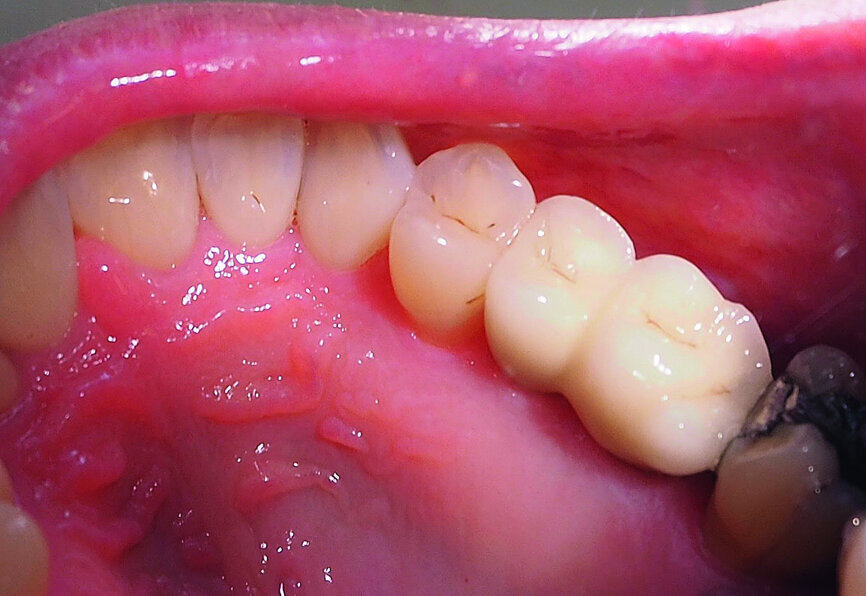

A 52-year-old female patient was concerned about the appearance of her smile. Her upper right first molar and second premolar had been missing for several years (Figs. 1 and 2). She was otherwise a fit and healthy non-smoker.

Fig. 1: The patient’s upper right first molar and second premolar had been missing for several years.